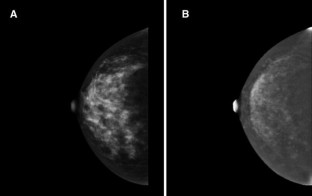

Fig. 1